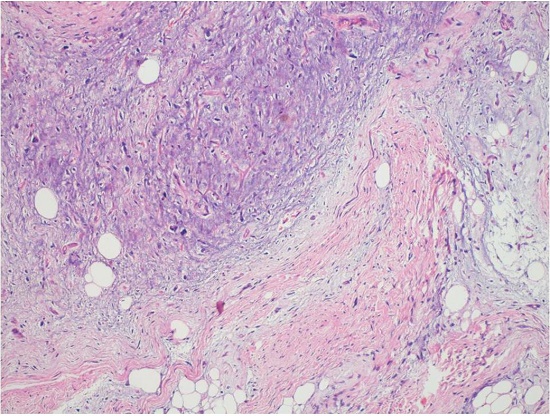

The specimen was extensively sampled to demonstrate the pathology, and a spectrum of pathological changes was documented. The smallest nodules (both attached and freely floating) showed multiple lobules of mature adipocytes with thin fibrous septa. The larger the masses, the more the thickness, complexity, number of septa, and number of septal and atypical adipocytic cells and lipoblasts increased (Figures 4A-4C and 5). The large nodules showed only a few lobules of mature fat and dominantly fibrocollagenous areas, giving rise to a sclerosing pattern (Figure 5). The largest nodule showed well-differentiated morphology with central areas of myxoid degeneration and atypical spindle cells in a myxoid matrix (Figure 6).

The septal cells were moderate to highly pleomorphic, singly scattered, spindle-shaped with hyperchromatic nuclei, and inconspicuous to occasional prominent nucleoli and wispy eosinophilic cytoplasm (Figure 7A). Many of these cells displayed bizarre morphology, and giant cells and floret-like cells were also noted (Figure 7B). The larger nodules also showed atypical adipocytes with hyperchromatic nuclei and many scattered univacuolated and multivacuolated lipoblasts (Figure 7C). Mitotic figures were occasional (2-4/10 high-power field); necrosis was absent. Immunohistochemistry for MDM2 (Figure 7D) and S100 showed nuclear positivity in the atypical septal cells, lipoblasts, and many of the mature-looking adipocytes.

CD34, Desmin, SMA, and βcatenin were negative in the tumor cells. The cecal bulge showed an endoluminal liposarcoma arising within the submucosa and stretching the overlying mucosa. The remaining ileum, ileocecal valve, and the colon did not reveal any mucosal pathology. The diagnosis of well-differentiated liposarcoma, adipocytic and sclerosing subtypes was rendered with the suspicion that the exophytic masses appeared to arise from the appendices epiploicae, which was consistent with the diagnosis of liposarcomatosis. The spectrum of changes was mostly corroborated by the size of the mass with the larger mass showing thicker septa, fewer number of adipocytes, and an abundance of atypical septal cells, atypical-looking adipocytes, and lipoblasts. Only few of the smaller nodules showed a morphological pattern similar to large nodules in terms of septal thickness and complexity.